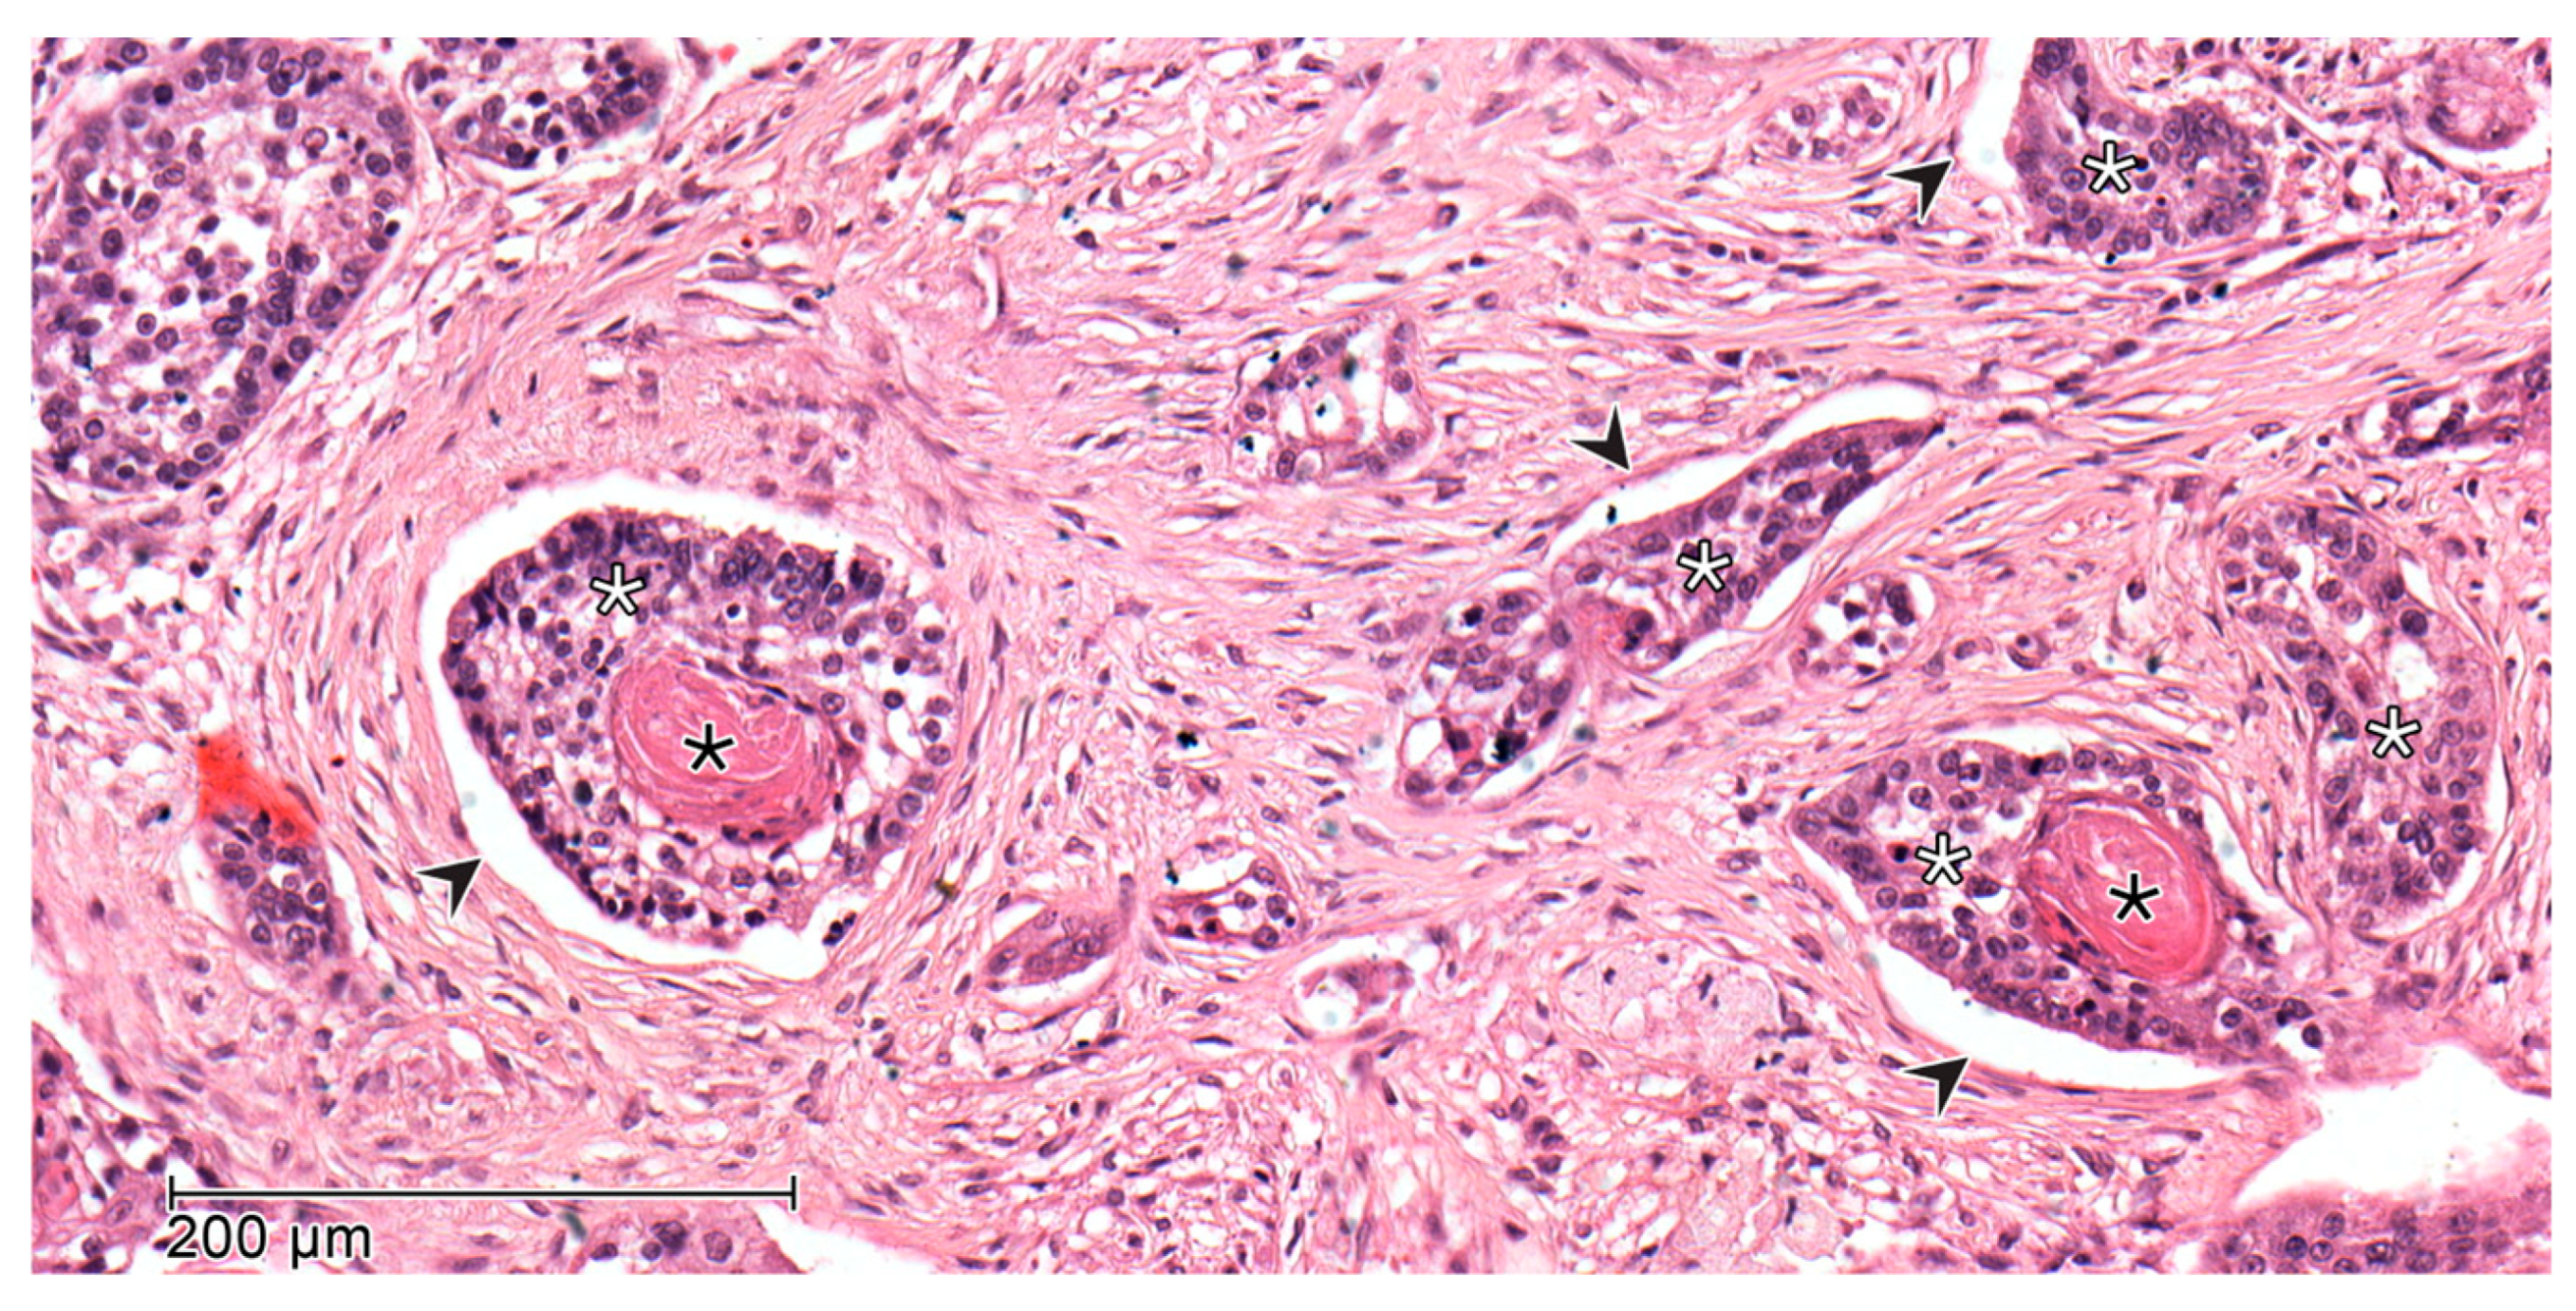

2.2. Histopathology